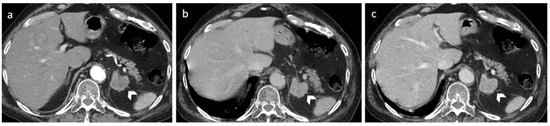

2.4. Cyst